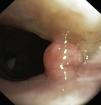

One patient had an epiglottis and vocal cord involvement and 3 patients had more extensive lesions: larynx and trachea in one case, pharynx, larynx and trachea in another case and one with a more exuberant and extensive form involving nasal cavity, pharynx, larynx, trachea and bronchus (Figs. 1–7).

In our department, all the patients were submitted to diagnostic and therapeutic bronchoscopy for their papillomatosis (Figs. 2, 4 and 7B). Depending on the location, degree of obstruction, extension and number of the lesions, multiple and combined procedures were needed accordingly. Neodymium yttrium aluminum garnet (Nd:YAG) laser and electrocautery were used for hemorrhagic lesions, wire loop electrocautery was used for polyploid papillomatas with cryotherapy at the tumor base to prevent regrowth. Due to the rapid recurrence rate, local administration of cidofovir at the base of the lesions was also tried.

| Endoscopic findings | Multiple polyploid papillomas in the nasal fossa, pharynx, larynx and proximal trachea | Larynx papillomas | Papilloma of the left vocal cord | Multiple polypoid papillomas of the larynx and proximal trachea (Figs. 6 and 7) |

| Significant obstruction of the trachea (>80%) | Exophytic mass obstructing 80% of the tracheal lumen (Fig. 3) | |||

| 1° line endoscopic treatment | Removal of the tracheal mass by an electrocoagulation snare | Removal of the tracheal mass by an electrocoagulation snare (Fig. 4) | Intralesional administration of cidofovir at the left vocal cord (Fig. 5) | Nd:YAG laser vaporization in the larynx and tracheal lesions (Fig. 8) |

| Coagulation of the tracheal tumor base with Nd:YAG laser (Fig. 2) | Photocoagulation of the tracheal lesions with Nd:YAG laser (Fig. 4) | No complications | Local administration of cidofovir at the base of the tracheal papillomas | |